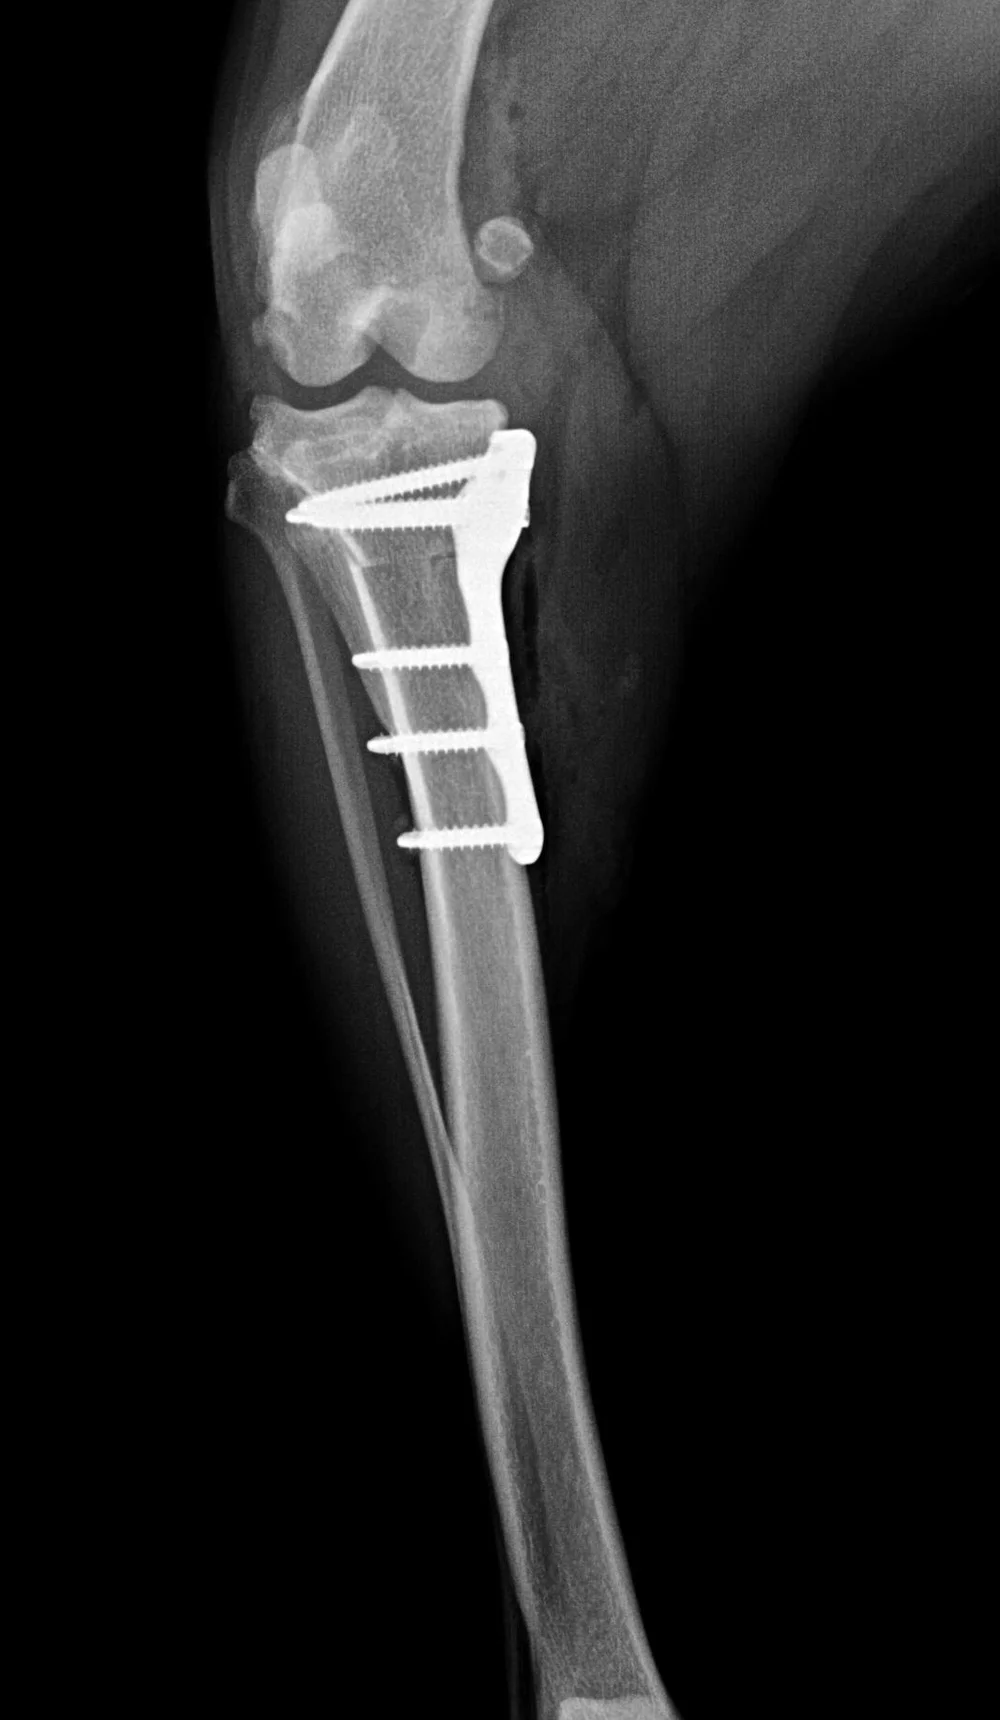

tplo Postoperative view of a TPLO Veterinary Surgical Specialists Does Pet Insurance Cover Tplo Surgery — does pet insurance cover tplo surgery for my dog? — in short, yes, many pet insurance companies do cover tplo surgery. Read on to learn more about tplo in. — tplo (tibial plateau leveling osteotomy) surgery has gained significant attention in veterinary medicine for addressing cranial cruciate ligament (ccl) injuries in dogs. This scenario is more. Does Pet Insurance Cover Tplo Surgery.

tplo Postoperative view of a TPLO procedure from the front Does Pet Insurance Cover Tplo Surgery — pet owners should examine the policy to confirm that tplo surgery is explicitly mentioned as a covered procedure. As with any medical procedure, it is natural for dog owners to have questions and concerns. Whether your pet insurance will cover the cost of tplo surgery for your dog will depend on your specific policy coverage. — tplo. Does Pet Insurance Cover Tplo Surgery.